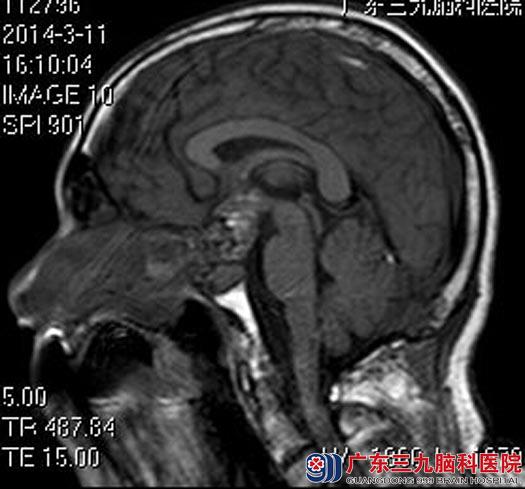

术后,陈先生的视力逐渐好转,出院时,他的视力基本恢复正常。术后病理结果:垂体促性腺激素腺瘤伴卒中。

手术后